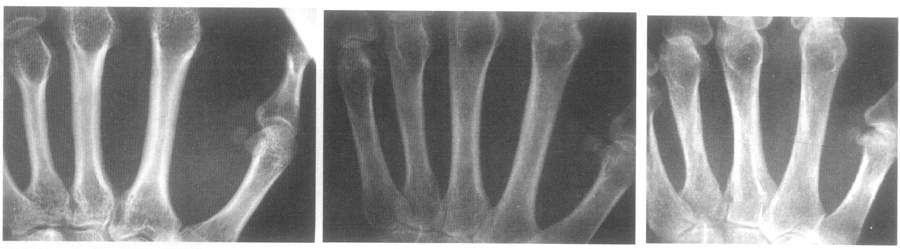

К начальным проявлениям (I–II стадия по Kellgren) относятся заострения или небольшие остеофиты на краях суставных поверхностей с нерезким субхондральным остеосклерозом; мелкие, субхондрально расположенные кисты при нормальной или слегка суженной суставной щели; мелкие кальцификаты в мягких тканях в области боковых краев суставных поверхностей костей (рис. 12).

Выраженные изменения (III–IV стадия по Kellgren) включают крупные остеофиты и деформацию краев суставных поверхностей, значительное сужение суставных щелей, субхондральный остеосклероз, кисты со склеротическим ободком, краевые дефекты суставных поверхностей (псевдоэрозии суставных поверхностей костей). Костные выступы на суставной поверхности одной кости могут вклиниваться в сочленяющуюся суставную поверхность другой кости и формировать типичный для ОА мелких суставов кистей симптом "летящей чайки" (рис. 13). Крупные остеофиты на краях суставных поверхностей, расположенные перпендикулярно оси дистальной фаланги, образуют другой характерный симптом "перевернутого Т". Обычно краевые дефекты костной ткани окружены зоной остеосклероза.

Остеофиты, кальцификаты и перифокальное уплотнение мягких тканей в краевых отделах суставных поверхностей образуют узелки Гебердена в дистальных межфаланговых суставах и узелки Бушара в проксимальных межфаланговых суставах.